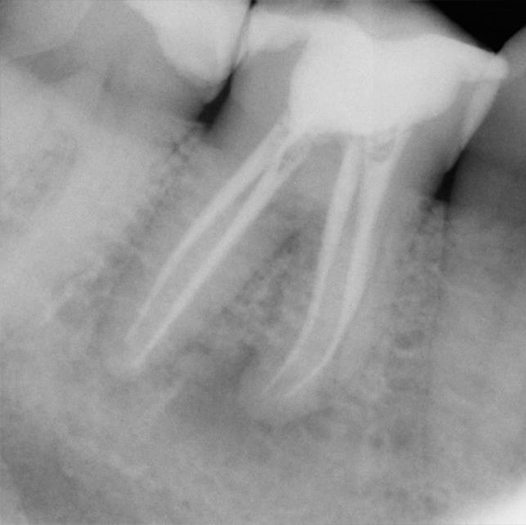

After

After Root Canal treatment